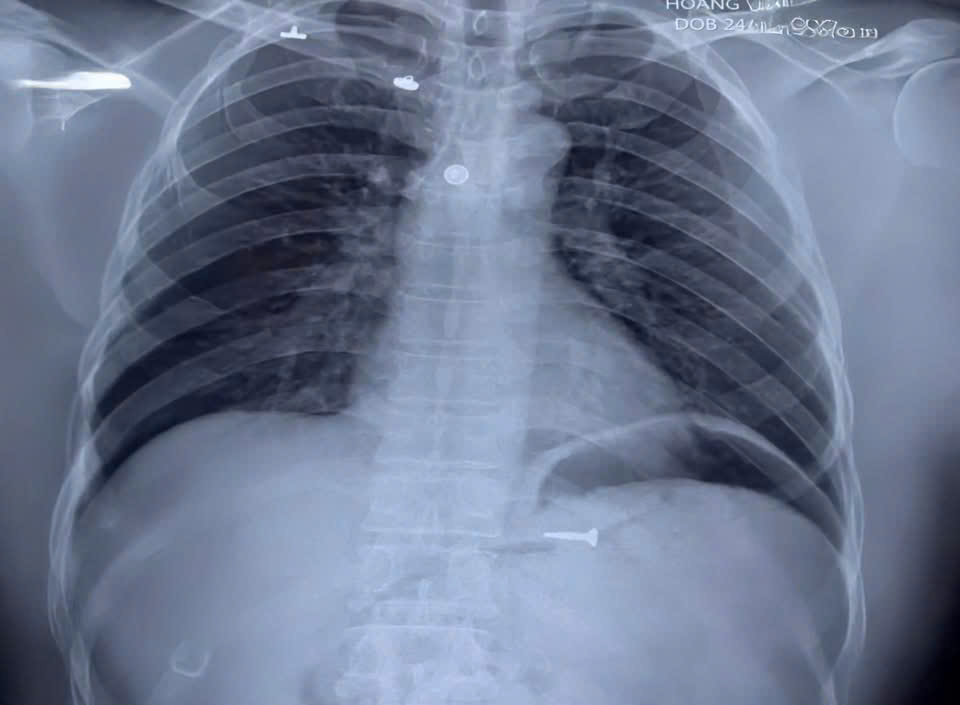

Ngay sau khi tiếp nhận, các bác sĩ của Khoa Nội tiêu hóa – Máu bệnh viện Quân y 105 đã nhanh chóng thăm khám và chỉ định chụp X-quang bụng. Kết quả hình ảnh cho thấy một vật thể kim loại sắc nhọn nằm tại vị trí dạ dày. Nhận định đây là tình huống khẩn cấp, nếu dị vật di chuyển xuống ruột non có thể gây thủng ruột, chảy máu hoặc gây nhiễm trùng ổ bụng nghiêm trọng, kíp trực tại Khoa Nội Tiêu hóa – Máu đã quyết định thực hiện nội soi can thiệp cấp cứu để lấy dị vật. “Cuộc săn” dị vật qua ống mềm Dưới sự chỉ đạo của chỉ huy Khoa, kíp nội soi gồm các bác sĩ và điều dưỡng dày dặn kinh nghiệm đã tiến hành thủ thuật.